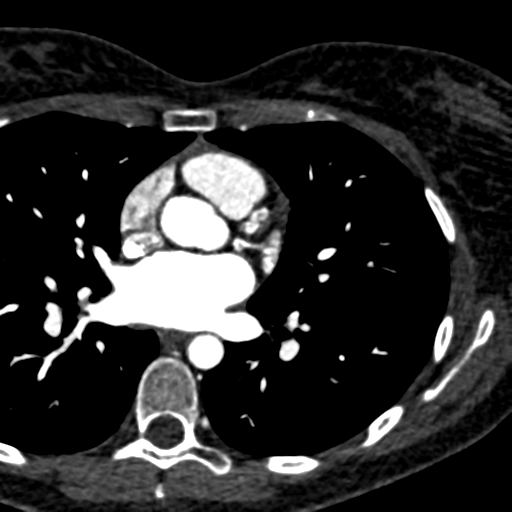

What sign is this?

What is the anatomy of the structure associated with this sign?

Pericardium Normal Anatomy

Radiographic Features ( Fig. 2.80 )

67-year-old male with history of prosthetic aortic valve stenosis, now with dyspnea on exertion and lower extremity swelling

Vertical retrosternal opaque stripes representative of possible pericardial effusion (“oreo cookie sign”).